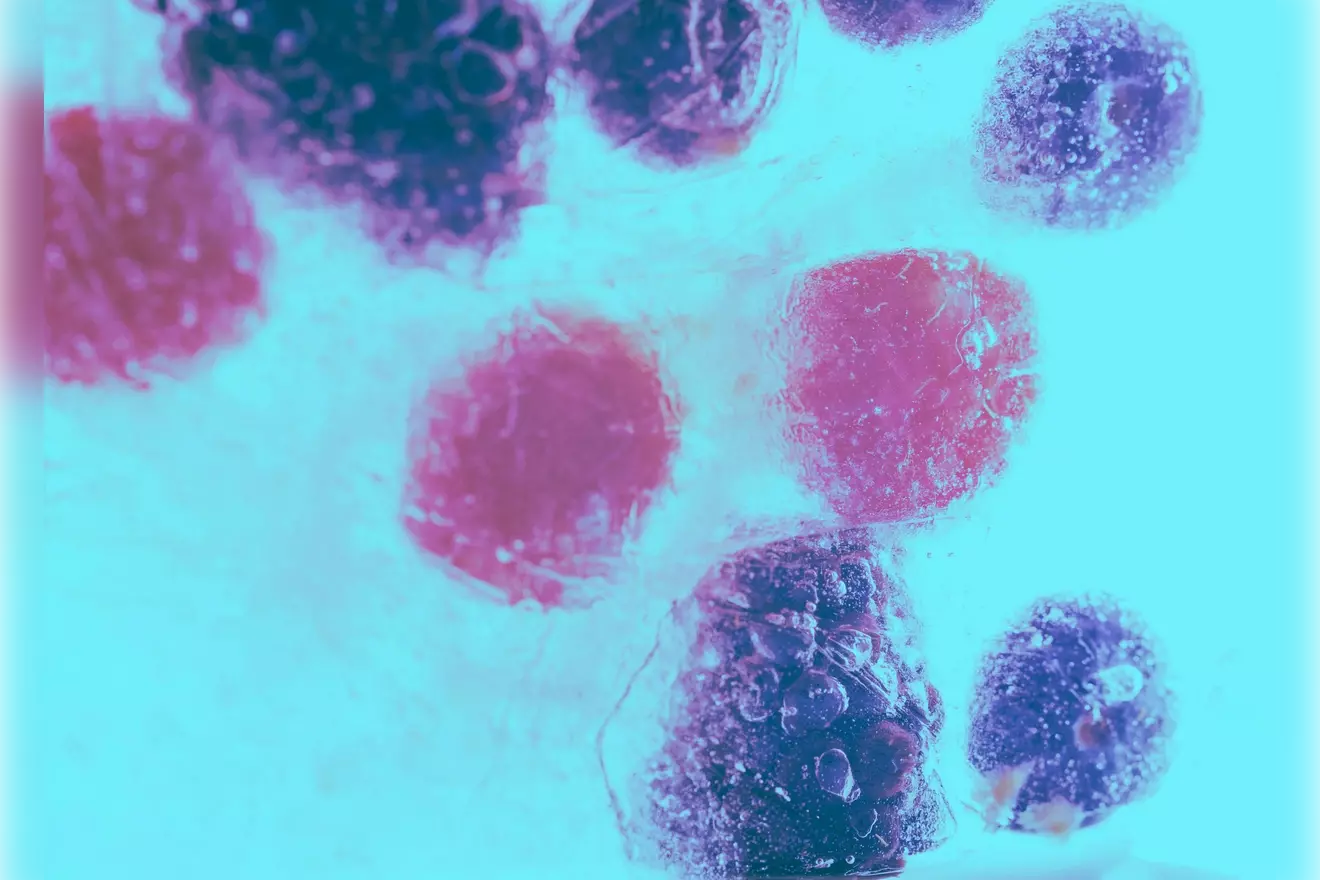

B Cell Malignancies: Leukemias and Lymphomas

B cell malignancies are cancers that start in B cells. They can be different in how they show up and how serious they are.

- Chronic lymphocytic leukemia (CLL) is a common B cell cancer in adults. It makes a lot of B cells in the blood and bone marrow.

- Diffuse large B cell lymphoma (DLBCL) is a fast-growing lymphoma. It needs quick treatment, often with chemotherapy and special medicines.